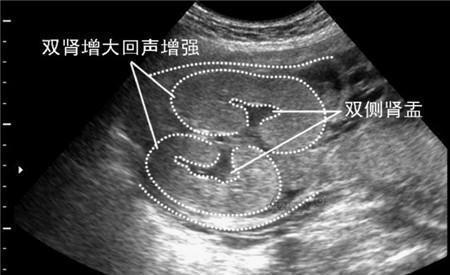

![]() 第三、如果四维彩超结果上有双侧肾盂未见明显分离,那么很高几率是女宝宝。如果是双侧肾盂见明显分离,那么很高几率是个男宝宝。这个是最容易判断生男生女的大排畸数据,准妈妈如果您做了大排畸可以仔细在B超单上找到这几个字“肾盂分离”或者是“肾盂无明显分离”。